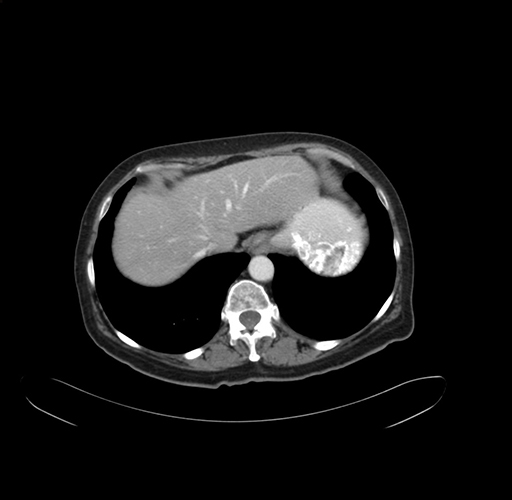

Pre-Chemo: Axial Venous

Axial Venous